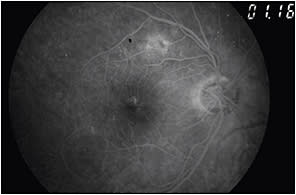

Perfusion status. The perfusion status of the macula and retinal periphery with ischemia (Figures 13 and 14) indicates a poor prognosis with no beneficial treatment. Such cases can present as a large foveal avascular zone (FAZ) or a FAZ with irregular borders.

Figure 13. Fundus photo of featureless retina with signs of macular ischemia. BCVA was counting figures.

Figure 14. Fundus FA of the patient in Figures 12 and 13 shows a large FAZ and capillary dropout.

The presence of significant nonperfusion of the retinal periphery (Figures 15 and 16) is a prognostic factor for proliferative diabetic retinopathy, which requires prompt panretinal laser photocoagulation. Placing laser burns in nonperfused areas of the retinal periphery when treating PDR is recommended to preserve the visual fields as much as possible, especially in patients with compromised visual fields, such as those with glaucoma.